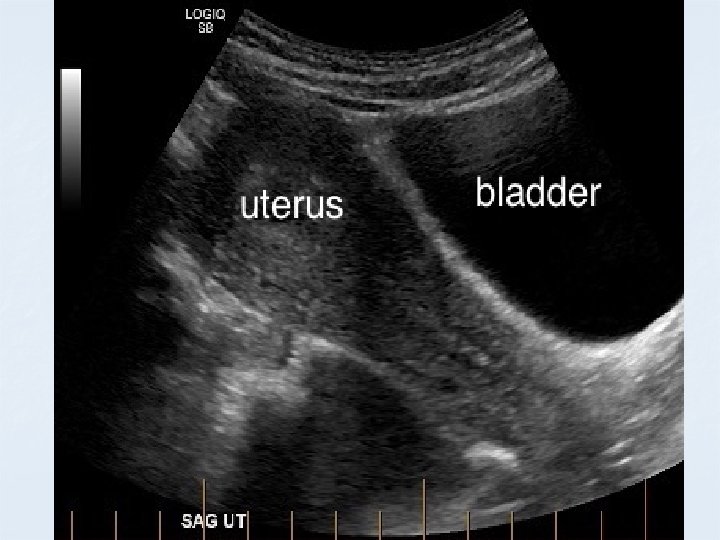

Pelvis sonogram TS UB /Uterus/ Ovary